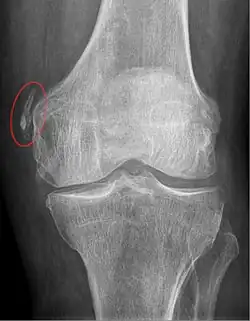

Diagnosis is typically made on radiographs demonstrating the Pellegrini-Stieda syndrome sign accompanied by pain or restriction of range-of-motion of the knee joint.[2] Pellegrini-Stieda syndrome sign is typically described by a longitudinally linear opacity, which is a process that is describes characteristic of calcification in the soft tissue located medial to the medial femoral condyle.[2] This calcification seen on imaging represents the ossification of the medial collateral ligament, which typically does not develop until approximately three weeks after the initial injury.[2]It is important to note to distinguish this radiographic finding from that of a medial femoral condyle avulsion fracture, which is an injury in which a pulling force of a tendon or ligament fractures away a piece of the bone from its attachment site.[2]

Alternative classification syndrome for Pellegrini-Stieda lesions of Type 1 through Type 4 based on their location:[2]

- Type 1- is referred to as a beak-like appearance and describes the ossification arising from the femur and extending inferiorly in the medial collateral ligament.

- Type 2-is defines a tear-drop pattern, localized within the medial collateral ligament without any attachment to the femur.

- Type 3-presents as an elongated ossification superior to the femur lying in the distal adductor magnus tendon.

- Type 4-is also characterized as a beak-like appearance arising from the femur. However, there are some cases where this ossification extends into both the medial collateral ligament and adductor magnus tendon. In then, the original attribution of the syndrome to the medial collateral ligament may now be outdated as many publications have suggested concomitant and even sometimes preferential involvement of the adductor magnus tendon, medial head of the gastrocnemius, or medial patellofemoral ligament.[2]